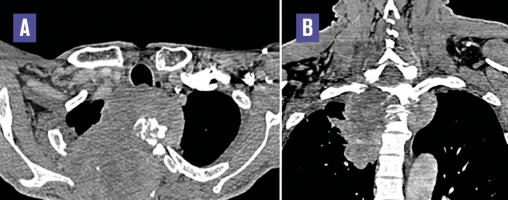

Cet homme de 52 ans, fumeur non sevré, consultait pour une douleur dorsale supérieure droite depuis 3 mois et un déficit moteur des 4 membres d’installation progressive. L’examen clinique notait une tétraparésie spastique et une dyspnée de stade IV. La tomodensitométrie (TDM) thoracique (fig. 1 ) montrait un processus tumoral de l’apex pulmonaire droit envahissant les deux premières côtes homolatérales ainsi que les deux premières vertèbres dorsales. Le diagnostic de la tumeur de Pancoast-Tobias était retenu. Une imagerie par résonance magnétique (IRM) médullaire était réalisée, montrant l’extension tumorale endocanalaire et la compression de la moelle épinière (fig. 2 ).

La tumeur de Pancoast-Tobias se situe à l’apex pulmonaire, infiltre par contiguïté les tissus de la paroi thoracique apicale (côtes, vertèbres) et peut envahir l’orifice thoracique supérieur.1 Elle cause douleur thoracique, névralgies cervicobrachiales, syndrome de Claude-Bernard-Horner et atrophie musculaire du membre supérieur ; avec parfois un œdème du membre supérieur (par thrombose de la veine sous-clavière), et des signes de compression médullaire (par extension tumorale endocanalaire).1 La TDM fait le diagnostic, analyse les rapports de la tumeur avec les structures adjacentes, détecte une thrombose veineuse (notamment de la sous-clavière), et analyse l’extension tumorale locorégionale et à distance. L’IRM cherche une souffrance médullaire et analyse l’orifice thoracique supérieur. Le diagnostic histologique conditionne la décision thérapeutique. Il s’agit fréquemment d’un carcinome de stade T3 ou T4 de la classification TNM.1, 2 Une chimio-radiothérapie néoadjuvante suivie d’une résection tumorale complète, même en cas d’envahissement vertébral, permet un pronostic de plus en plus proche de celui d’un cancer pulmonaire non apical de stades similaires.2